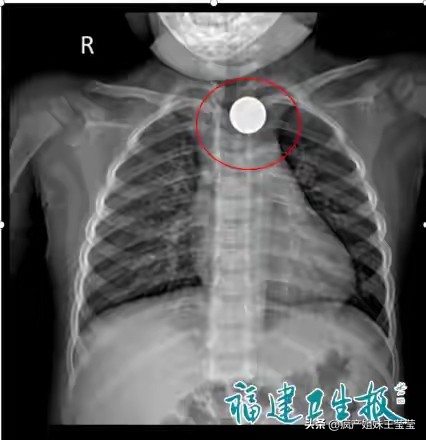

2岁宝宝正是爱把东西放嘴里的年纪,玩耍时不慎将硬币吞入,瞬间哭闹不止、呼吸困难。家长惊慌失措,紧急送医后,医生通过影像学检查发现硬币卡在食管入口,紧邻气道,稍有拖延就可能窒息。万幸的是,医护人员快速用内镜将硬币顺利取出,孩子转危为安。医生提醒,幼儿食管狭窄、黏膜娇嫩,硬币、纽扣、电池等小物件一定要远离孩子,切勿让孩子口含物品玩耍。